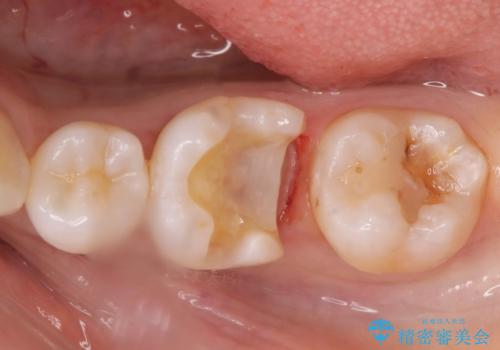

メタルの詰め物が取れた

- メタルインレーが取れてしまって来院。

虫歯が再発していたので拡大鏡下で取り切った後、e-maxインレーにて治療しました。

また、一番奥の歯も古い樹脂の治療がされていたため虫歯の予防のために樹脂を取り除き、う蝕がないことを確認してe-maxインレーで治療しました。